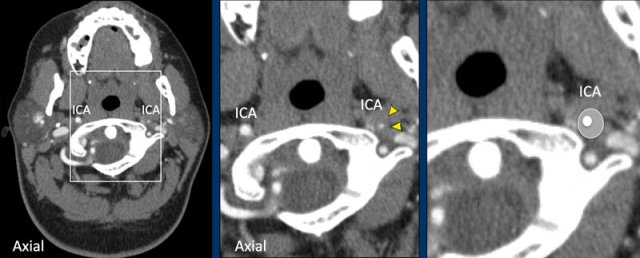

On CTA a dissection presents with the

following findings:

- On axial images there is an eccentric and narrowed lumen of the ICA.

- There is expansion of the ICA (↑ of the total diameter).

- The bulbus is spared unlike in atherosclerotic disease.

- A dissection generally stops prior to entering the skull.

String sign

In most cases a dissection will present with a flame-shaped appearance like in A, but when the lumen is less compressed and still partially patent you may get the "string sign" as in B.

Look below the skull base

When you consider the possibility of a dissection, t is important to study the axial images just below the skull base as in this case.

On the left side there is a normal ICA and ECA (the high density structure in between them is the styloid process).

On the right side we see a normal ECA and medial to the jugular vein is the dilated ICA (circle).

The lumen does not fill with contrast.

The combination of an occlusion in an enlarged and dilated ICA means that we are dealing with a dissection.